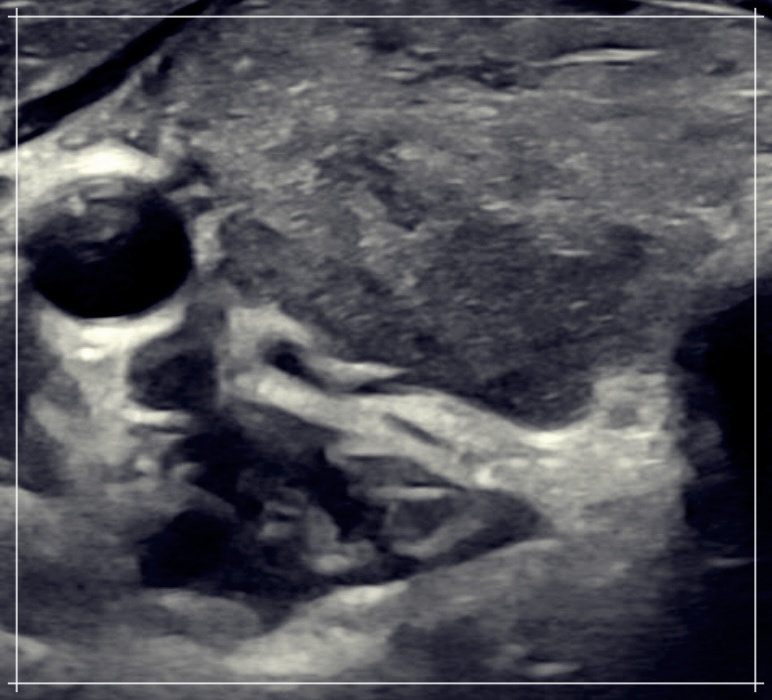

아급성 갑상선염은 갑상선의 염증으로 인해 발생합니다. 이로 인해 목 부위에 통증을 느낄 수 있으며, 통증은 귀나 턱까지 확산될 수 있습니다.

이 통증은 때로는 매우 심각해질 수 있으며, 일상생활에 지장을 줄 수 있습니다. 아급성 갑상선염에는 몸살 같은 증상, 발열, 피로감, 근육통, 식욕 부진 등 다양한 증상이 동반될 수 있습니다. 특히, 갑상선 호르몬의 과다 또는 부족으로 인해 심계항진 또는 심계부전이 발생할 수 있습니다. 이는 심장 박동수가 빠르거나 느리게 변하며, 흔들림, 불안, 피로감 등의 증상을 유발할 수 있습니다.

아급성 갑상선염의 정확한 원인은 아직 잘 알려져 있지 않습니다. 하지만, 바이러스 감염이 원인일 가능성이 크다고 알려져 있습니다. 특히, 호흡기 감염에 의해 발생하는 경우가 많습니다.